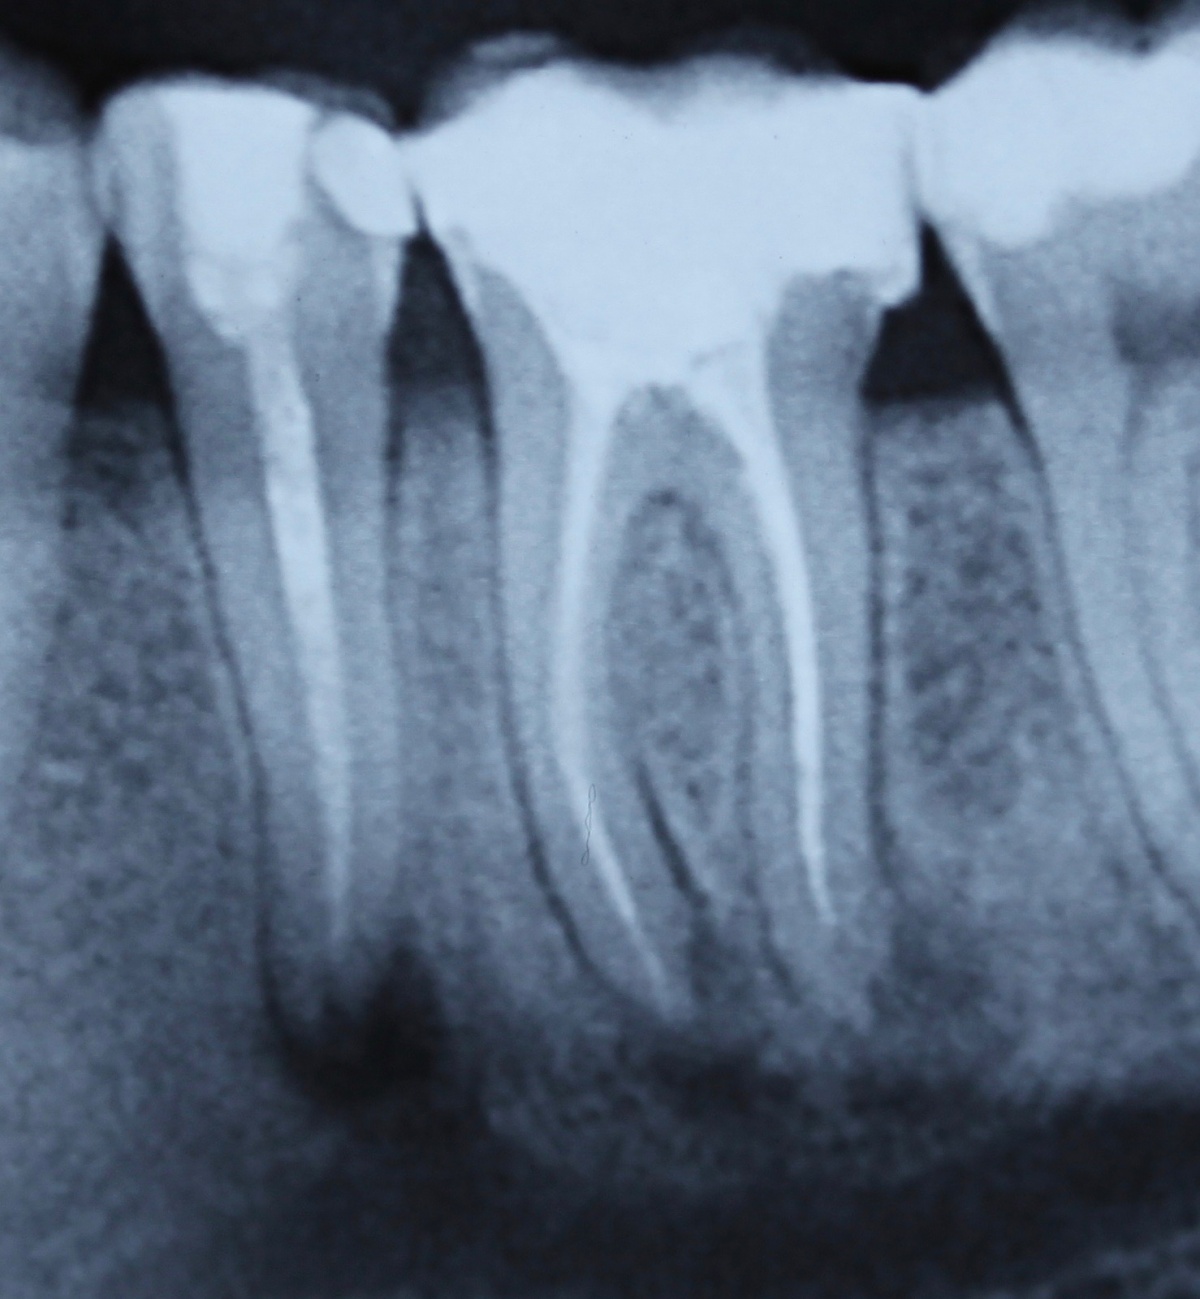

Durch eine Vielzahl von Studien konnte belegt werden, dass die Versorgung mit implantatgetragenem Zahnersatz eine bewährte Behandlungsoption darstellt. Gleichwohl zeigen viele Studien jedoch, dass – wie bei allen Therapiemaßnahmen auch – Komplikationen auftreten können. Diese haben im Allgemeinen biologische oder technische Ursachen. Als häufigste biologische Komplikation findet man die Mucositis (Abb. 1), die Entzündung der periimplantären Gewebe ohne Beteiligung des Alveolarknochens. Nach aktuellen Studien weisen ca. 30 % aller Implantate nach fünf Jahren eine Mucositis auf. Kommt es darüber hinaus zu einer Beteiligung des Alveolarknochens, liegt eine Periimplantitis vor (Abb. 2). Sie tritt nach fünf Jahren bei etwa 10 % der inkorporierten Implantate auf und ist durch den Verlust des periimplantären Alveolarknochens gekennzeichnet. Die Periimplantitis kann, je nach Schweregrad, zum kompletten Implantatverlust führen. Bei einem strategisch wichtigen Implantat kann daraus der Verlust der gesamten prothetischen Versorgung resultieren und eine operativ sowie finanziell aufwendige Neuversorgung erforderlich werden (Abb. 3).

Ziel ist es, durch die Entfernung von Gewebs- und/oder Zahnanteilen die Zugänglichkeit zu schwer zugänglichen parodontalen Defekten zu verbessern. Darüber hinaus kann durch diese Maßnahmen die Hygienefähigkeit verbessert und eine Neubesiedelung des Parodontiums durch die mikrobielle Plaque verhindert werden. Vor allem die Prognose von furkationsbeteiligten Molaren kann auf diese Weise deutlich verbessert werden. In einer vielbeachteten Studie aus dem Jahre 2001 haben Fugazotto und Mitarbeiter die Prognose von 701 resektiv behandelten Molaren untersucht und beeindruckende Ergebnisse erzielt. Nach 15 Jahren waren noch 678 Molaren (94,9 %) in situ und erfüllten die vorgegebenen Erfolgskriterien. So lautete dann auch die Kernaussage dieser Studie, dass bei richtiger Indikationsstellung resektiv behandelte Molaren mindestens die gleich gute Langzeitprognose wie Implantate haben. In diesem Zusammenhang sei erwähnt, dass die Voraussetzung für eine erfolgreiche resektive Therapie die erfolgreiche endodontische Behandlung ist. Wie später noch ausgeführt wird, haben sich gerade auf diesem Gebiet durch technische Neuerungen völlig neue Möglichkeiten ergeben, was die Prognose der resektiv behandelten Molaren weiter verbessern dürfte. Ein kleines Beispiel, wie durch derartige Behandlungsschritte eine Implantation verhindert werden kann, zeigen die Abb. 5 und 6, wo durch eine Hemisektion des mesialen Wurzelanteils am Zahn 46 und anschließende Versorgung mit einer kleinen Brücke von 45 auf 46 eine Implantatinkorporation unnötig wurde.

Idealerweise können mit den Maßnahmen der regenerativen Parodontalchirurgie durch Entzündungen verloren gegangenen Anteile des Parodontiums wiederhergestellt werden. Dazu stehen verschiedene Operationsverfahren zur Verfügung. Einen wissenschaftlich belegten Behandlungserfolg bieten insbesondere Maßnahmen der gesteuerten Geweberegeneration (GTR, Guided Tissue Regeneration) und die Anwendung von Schmelzmatrixproteinen. Da ein Erfolg dieser Maßnahmen ganz maßgeblich von der Defektmorphologie abhängig ist, gilt es eine strenge Indikationsstellung zu beachten. Als prognostisch günstig gelten dreiwandige vertikale Knochendefekte sowie Furkationsdefekte des Grades 2 bei Unterkiefermolaren. Bei der Anwendung der gesteuerten Geweberegeneration können verschiedene Barrieremembranen zum Einsatz kommen. Diese verhindern im Idealfall eine Besiedlung des Defekts mit den schnell proliferierenden Zellen des Epihels oder Bindegewebes und ermöglichen so eine Regeneration mit der Neuausbildung parodontalen Attachments. Eine Therapie mit gesteuerter Geweberegeneration ist technisch durchaus anspruchsvoll und sollte daher nur von parodontalchirurgisch geübten Operateuren angewendet werden. Der Erfolg einer solchen Maßnahme ist in den Abb. 7 und 8 dargestellt. Mittels einer ePTFE-Membran konnte der mesiale vertikale Defekt zur Ausheilung gebracht werden und zeigte sich auch nach fünf Jahren stabil. Vergleichbar gute Erfolgsraten können auch mit der Anwendung von Schmelzmatrixproteinen erzielt werden. Hier sei beispielhaft auf die Studie von Sanz und Mitarbeitern aus dem Jahre 2004 verwiesen, wo mit einem Schmelzmatrixprotein ähnlich gute Ergebnisse hinsichtlich dem Attachmentgewinn und der Reduzierung der Sondiertiefen wie mit Membranen erzielt werden konnte. Als vorteilhaft gegenüber Membranen hat sich die signifikant geringere Rate von Komplikationen gezeigt, zudem ist die Anwendung von Schmelzmatrixproteinen technisch deutlich einfacher.

Eine Schnittstelle zu den bereits ausgeführten parodontalen Voraussetzungen des Zahnerhalts ergibt sich bei kombinierten Paro-Endo-Läsionen beziehungsweise Endo-Paro-Läsionen. Zeigen konservative Behandlungsansätze bei den meisten dieser Befunde gute Ergebnisse, ist bei einem lokal ausgeprägten Knochenabbau zumeist die chirurgische Intervention zum Zahnerhalt notwendig (Abb. 11 und 12). Wichtig dabei ist die Unterscheidung der primären Ursache (primär endodontische oder primär parodontale Ätiologie) der Läsion und einem dieser Ursache angepasstem Behandlungsprotokoll.